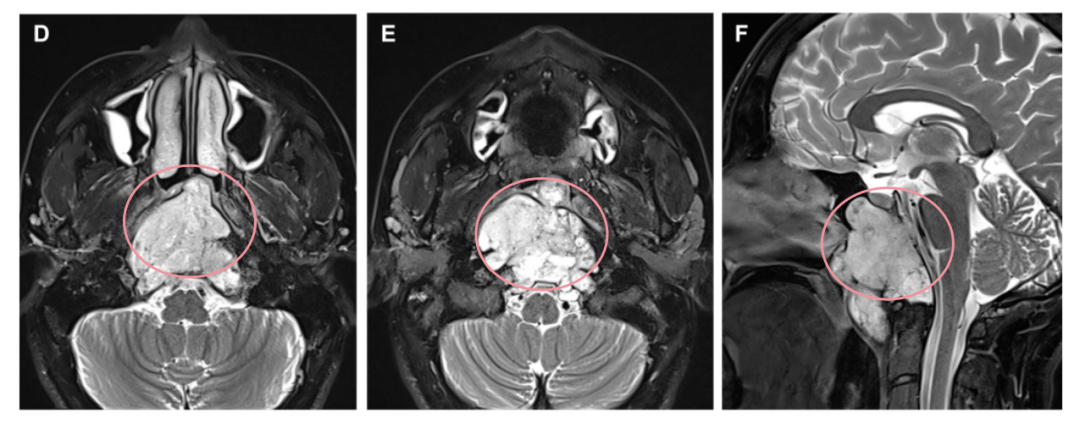

确诊斜坡脊索瘤后,在当地医院进行活检手术时意外损伤鼻中隔动脉,引发持续性鼻出血。未切除的肿瘤持续压迫脑干等重要结构,单是活检手术就造成血管损伤,若需进一步实施肿瘤切除手术,治疗难度大大增加。面对如此棘手的病情,Roger能否获得成功救治?

Roger鼻腔持续出血污染了手术视野,大幅增加误伤神经血管的风险;受损血管的修复也成为亟待解决的重要问题。较大的穿孔已破坏局部黏膜血供,导致使用黏膜瓣的传统修复方案不可行。

通过单鼻孔入路,福教授为Roger成功完成了手术,术后MRI显示肿瘤被完全切除。术中同样采用了鼻粘膜修复技术,保证了术后的生活质量。

术后MRI影像明确肿瘤全切情况,以及用于重建的自体脂肪